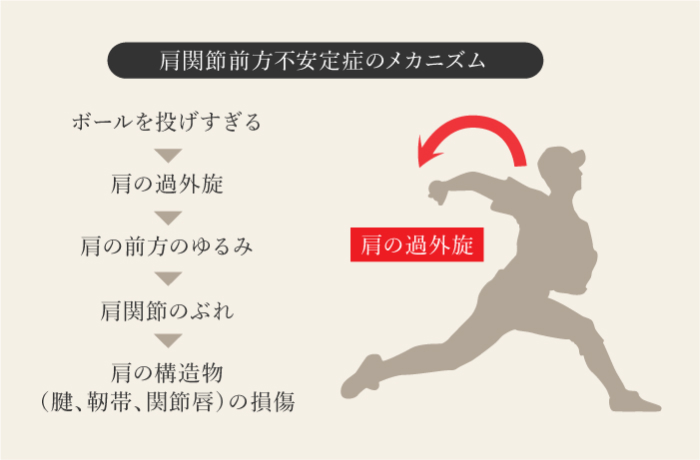

肩関節不安定症

-

肩の小さいずれや、肩の骨が安定していない状態で、「ルーズショルダー」とも言われ、靭帯や周囲の筋肉が弱くなったときに起こり、靭帯や筋肉が伸び過ぎて弱くなること